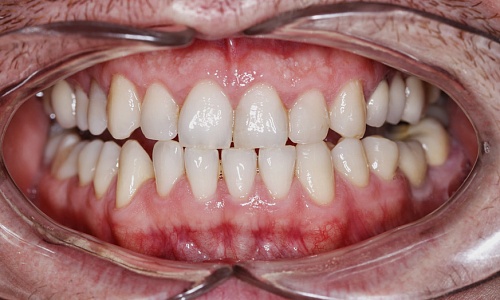

Cтабильный белоснежный здоровый результат от Александра Попова

Стоматолог-ортопед на Ленина 12